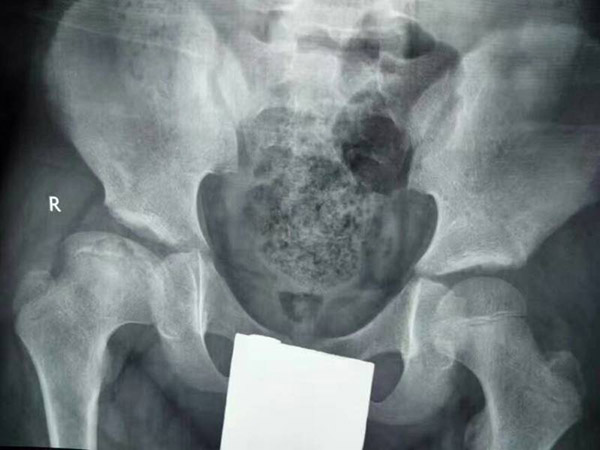

治疗中